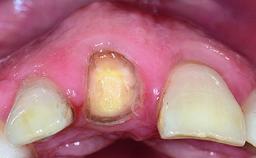

Replacement of a Missing Upper Left Central Incisor: Late Placement of an RC Bone Level Implant, CAD/CAM Zirconia Abutment

Eduardo R Lorenzana, Jason R Gillespie

A healthy 37-year-old female patient was referred for a consultation on the replacement of missing tooth 21 with an implant-supported restoration. She stated that several years previously the tooth had been traumatically avulsed following a motor vehicle accident. The tooth was replaced with a three-unit fixed partial denture (FPD) immediately afterwards. Over time, she became disillusioned with the FPD and looked for a different option, including orthodontic therapy. She presented still in her orthodontic appliances, with the pontic sectioned free from the FPD but attached to the archwire. Her orthodontist felt that orthodontic treatment had been successfully completed, but nevertheless referred her before removing the appliances in case adjustments were necessary.

Bone Volume Deficient horizontally, allowing simultaneous augumentation